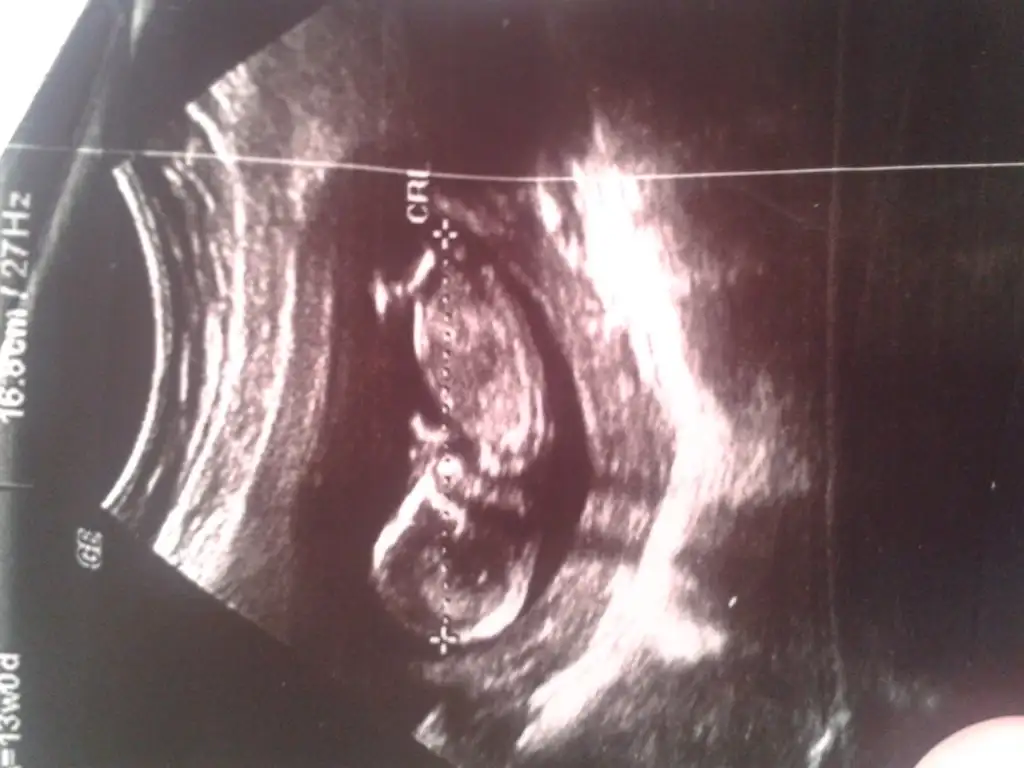

merhaba birkaç zamandır foruma bakıyorum şimdi yazmak nasip oldu bir kızım var Rabbim bağışlasın 19 aylık şimdide 13 haftalık hamileyim görüntüsü var doktor pozisyonu uygun değil daha çok erken diyerek söylemek istemedi açıkçası daha erken filan dedi yorumlaınızı bekliyorum